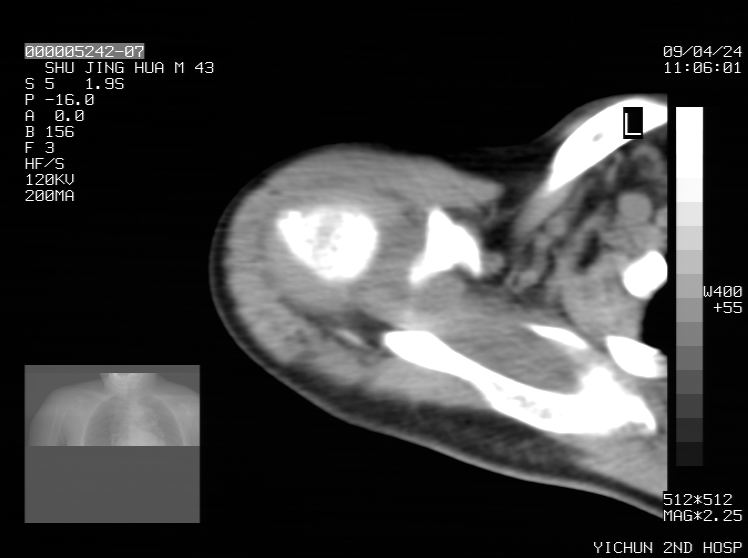

标题: CT19569:请会诊,女50岁,右肩疼痛数月 [打印本页]

标题: CT19569:请会诊,女50岁,右肩疼痛数月

钙化性肌腱炎

是指钙盐沉积在变性肌腱中的一种无菌性炎症,常见于肩关节的肩袖肌腱,引起肩部疼痛和活动受限。分为急性和慢性两种类型,急性型有肩关节突然出现急性疼痛的发作史,夜间可痛醒。